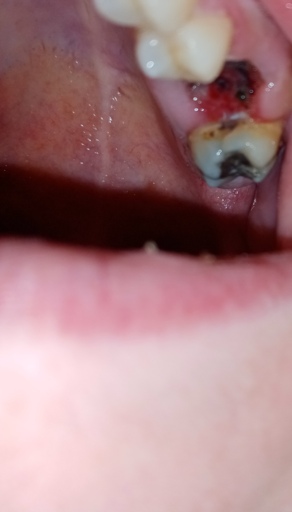

Is this normal healing of extraction sites

I had 2 wisdom and 2 molars removed as of now 5 days ago and these photos were taken on day 3, I was concerned that they may be infected, but there is no pain or outrageous swelling, no bleeding either and I can't really tell if there is a bad smell...